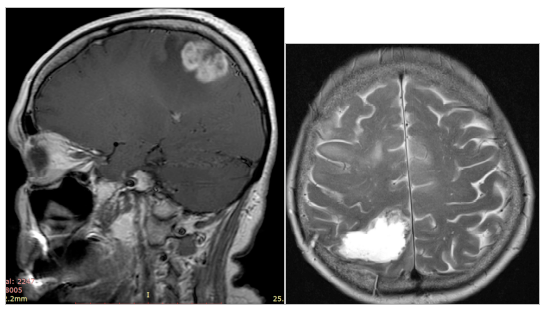

МРТ до операции

МРТ головного мозга после операции